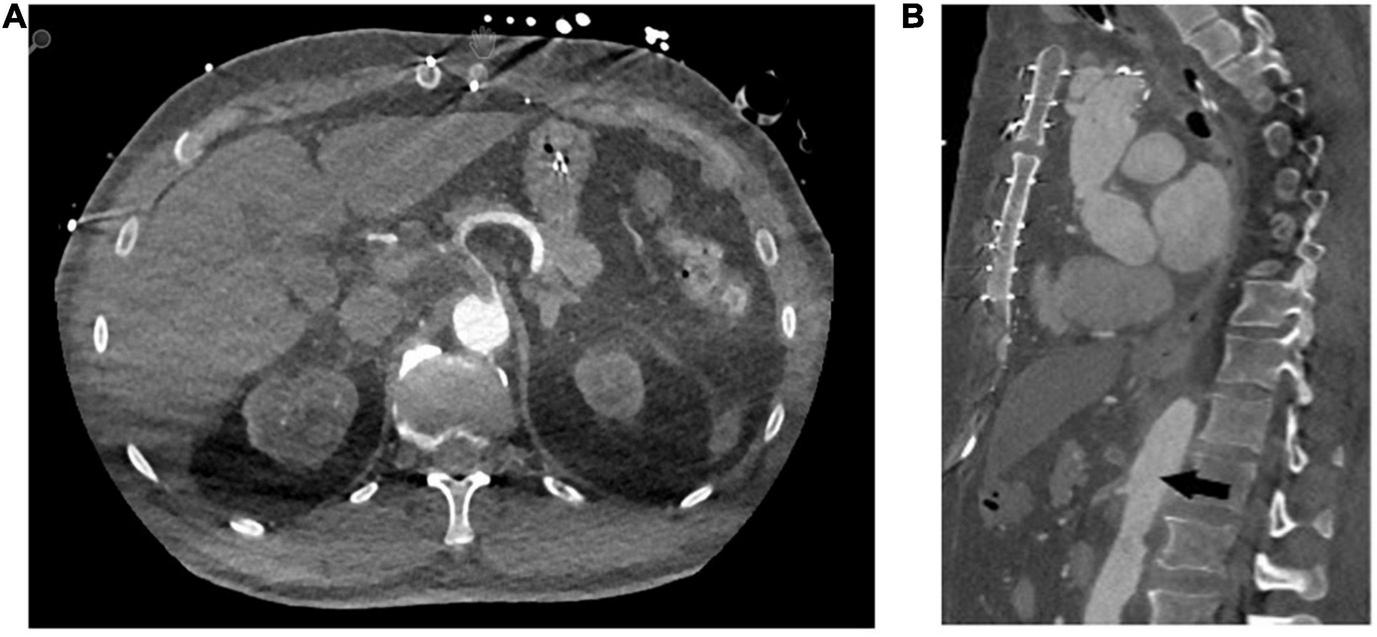

Thrombus embolisation occurred in four patients (21%). In the first, embolisation led to a subtotal occlusion of the coeliac trunk (Figure 2), the superior mesenteric artery and both renal arteries. Because of this patient frail state, we opted for an endovascular approach and were able to re-vascularise the superior mesenteric artery and both renal arteries via stent-graft [Advanta stent-grafts (Getinge Deutschland GmbH, Rastatt, Germany)] implantation. It was unfeasible to revascularise the coeliac trunk. Despite all our attempts, this patient developed severe visceral ischaemia and expired in multi-organ failure with circulatory depression. Embolisation in the second patient caused a total occlusion of the left renal artery entailing complete ischaemia of the left kidney. This patient’s medical history included complex interventions and operations of the renal arteries including an iliaco-renal bypass; therapeutic anticoagulation was the treatment of choice. This patient required permanent postoperative dialysis. The third patient’s embolisation caused infarctions in the liver and spleen and a subtotal occlusion of the ileocolic artery. A remaining thrombus was visible in the FET stent-graft that had not resolved in a control CTA scan despite therapeutic anticoagulation. Therefore, a conventional stent-graft (Relay NBS Terumo Aortic, Vascutek Ltd., Inchinnan, United Kingdom) was put in place to over-stent the thrombus. During another control CTA scan, the thrombus had disappeared. In the fourth and last patient, the thrombi embolised inside the coeliac trunk, the splenic, gastroduodenal, and left gastric arteries causing no clinically relevant malperfusion or organ infarction. After initiating therapeutic anticoagulation, the thrombi were no longer visible during the follow-up CTA scan.

FIGURE 2

Representative computed tomography angiography images of distal embolisation of the in-stent thrombi to the coeliac trunk (A) axial plane (B) sagittal plane.